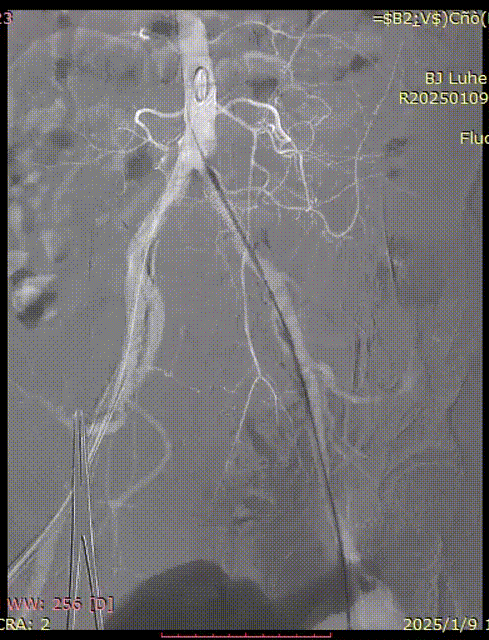

术前下肢动脉造影

处理后下肢动脉造影